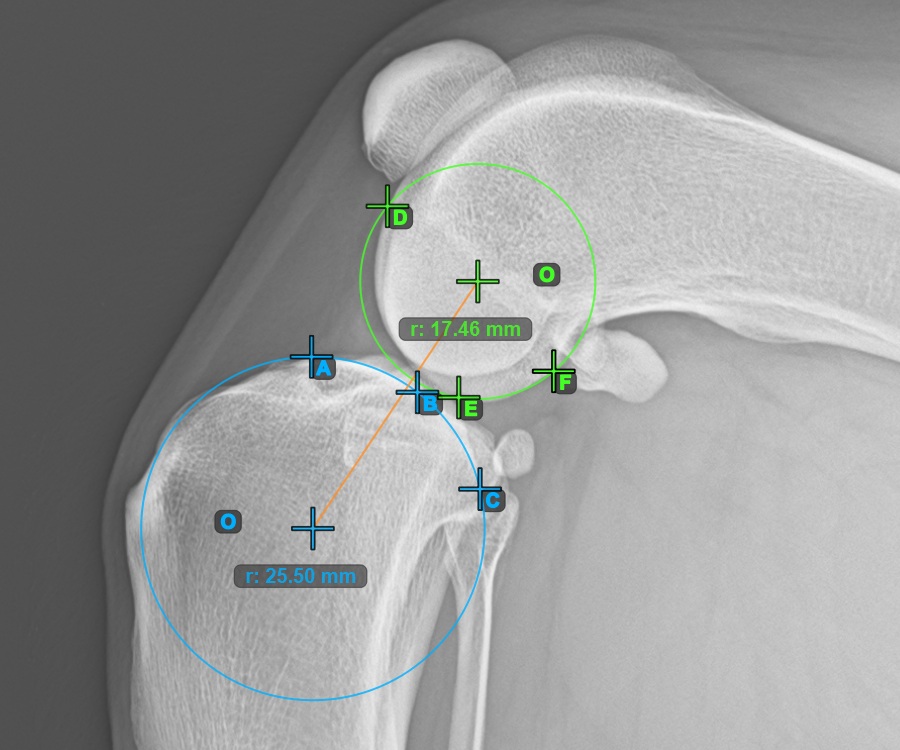

Markieren Sie einen Punkt vor dem Gelenk auf der gemeinsamen Tangente zwischen den beiden Hauptkondyluskreisen. Eine Linie wird automatisch durch den markierten Punkt gezogen.

Das Bild unten zeigt die typische Platzierung des Punkts auf der gemeinsamen Tangente zwischen den beiden Kreisen.